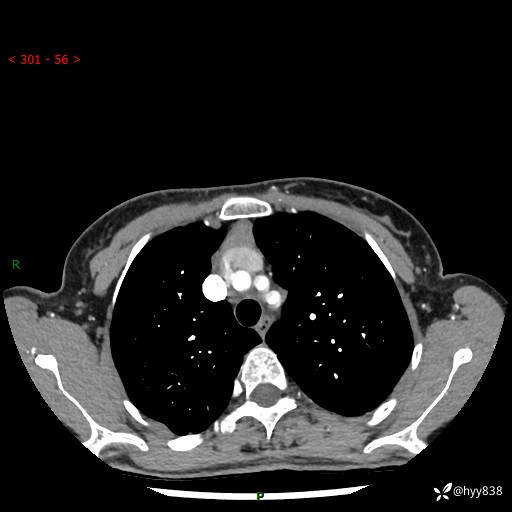

增强动脉期+静脉期